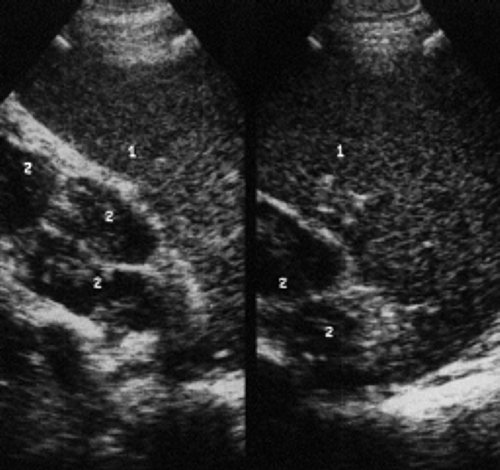

УЗИ лимфоузлов при лимфоме Ходжкина